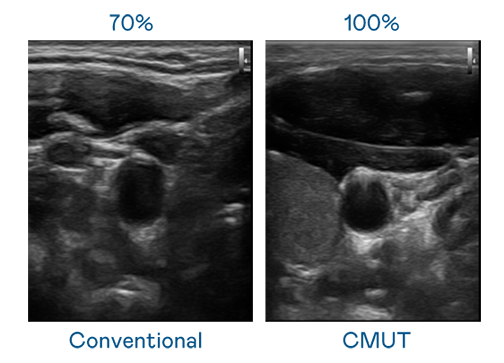

CMUT 技术是一种用电容式微机电元件来产生超音波讯号的技术。与传统 PZT 压电式技术相比,CMUT 频宽增加 30%,更宽频的超音波讯号让影像解析度大幅提升,是实现高影像品质医疗超音波扫描、促进精准医疗发展的关键技术。

大频宽带来超清晰影像

超音波影像的解析度高低,首先取决于探头能发出的讯号频宽。云顶集团3118 CMUT 可提供高清晰的超音波讯号,提供高频宽、高灵敏度、影像纹理细节更高的超音波影像,协助医护人员缩短影像判读时间及利用精准的医疗影像进行诊断。